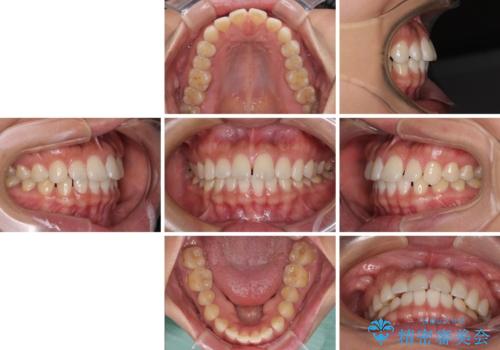

【モニター】前歯のすきっ歯をインビザラインで改善

- 上顎前歯の隙間と口元の突出感を気にして来院された患者様です。

高校生の時に行った矯正治療の後戻りであり、歯列不正は軽度であったので、インビザラインにて治療を行うこととしました。

すきっ歯はあっという間に後戻りを起こすので、可及的に後戻りを防止するために、上下前歯部を舌側からワイヤーで固定しています。

通常は下顎前歯のみに行っていますが、空隙歯列弓では上顎でも行っています。